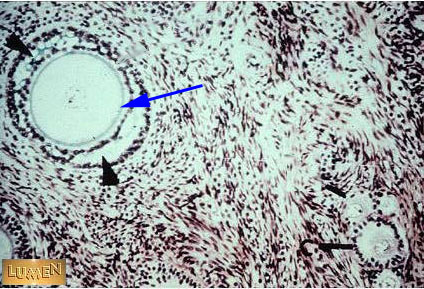

Zona Pellucida

(Grey line surrounding egg)